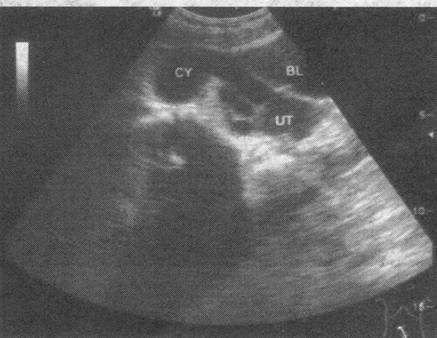

[单选题]女,27岁,下腹部疼痛数月。体检:右侧附件区增厚、增大,B超检查如图所示,最可能的诊断为()。A . 右侧卵巢囊肿B . 右侧输尿管扩张C . 右侧输卵管积液D . 盆腔积液E . 右侧卵巢肿瘤

[单选题]患者女27岁,下腹部疼痛数月,体检:右侧附件区增厚、增大,B超检查如图所示应诊断为()A .右侧卵巢囊肿B .右侧输尿管扩张C .右侧输卵管积液D .盆腔积液E .卵巢癌

[单选题]女性,26岁,下腹部疼痛数月。妇科检查右侧附件区增厚、增大,超声检查如图所示,最可能的诊断为A.右侧卵巢黄体囊肿B.右侧输尿管扩张C.右侧输卵管积液D